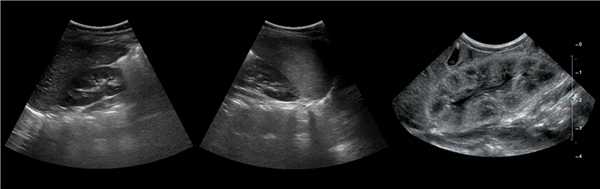

Рисунок. На УЗИ почечное ложе слева пустое (1). Обе почки расположены справа, срастаются полюсами (2, 3). Заключение: Аномалия взаиморасположения почек — I-образная удвоенная правая почка.

Рисунок. На УЗИ в малом тазу (мочевой пузырь — акустическое окно) определяются почки связанные узким перешейком (1, 3); дифференцировка паренхимы сохранена, кровоток прослеживается до капсулы (2, 3). Заключение: Аномалия взаиморасположения почек — сращение нижних полюсов тазово-дистопированных почек.